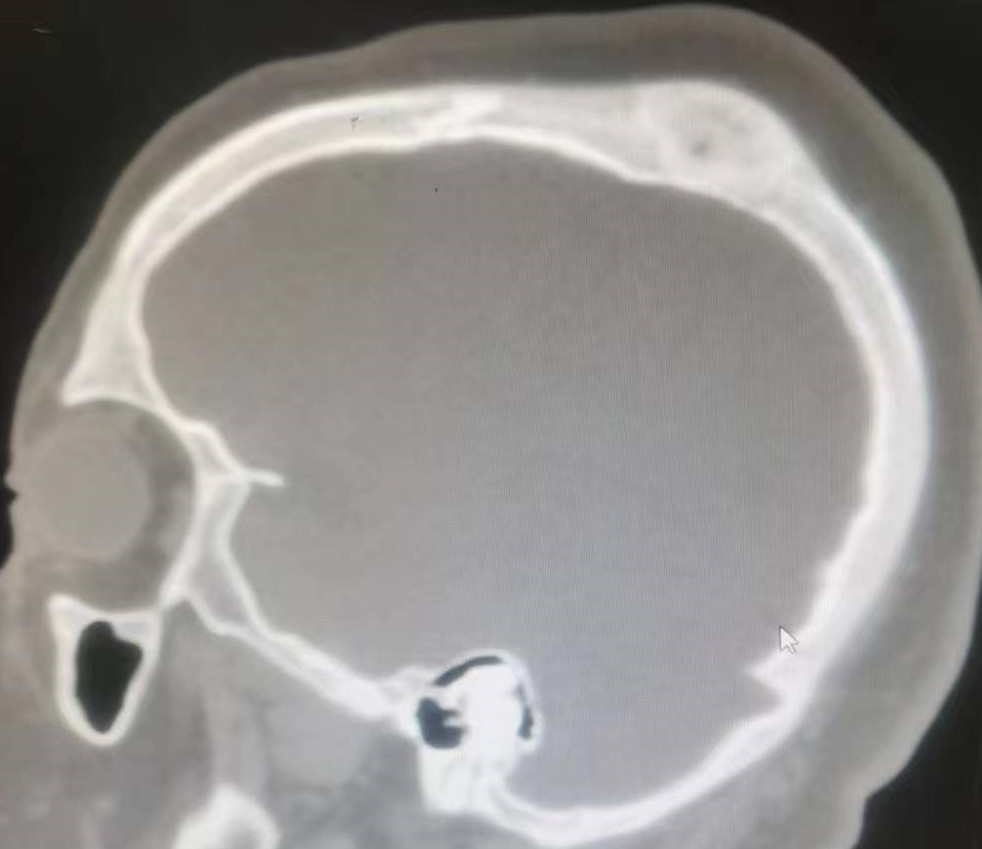

某23歲的患者在體檢時,被發(fā)現(xiàn)存在顱底鞍區(qū)的骨纖維異常增生癥,見下【圖-1】。當(dāng)時,患者并沒有任何不適癥狀。多數(shù)醫(yī)師的初步建議是保守治療,觀察隨訪。在隨后的七年中,患者進(jìn)行了間斷的復(fù)查,病變并沒有明顯的進(jìn)展,見下【圖-2】【圖-3】。由于某些原因,近幾年患者沒有再進(jìn)行復(fù)查,但最近的CT掃描結(jié)果顯示,病變?nèi)晕从忻黠@變化,見下【圖-4】。近期,患者感到視物稍顯模糊,但眼科的檢查結(jié)果顯示,其視力和視野均未發(fā)生變化。唯一的變化是患者的近視度數(shù)增加,現(xiàn)在約為400多度。骨纖維異常增生癥的進(jìn)展通常較為緩慢,可能持續(xù)數(shù)年或十幾年都沒有明顯變化。因此,對于沒有明確癥狀的患者,保守觀察和隨訪仍然是推薦的最佳策略。因此,繼續(xù)建議患者進(jìn)行觀察隨訪。